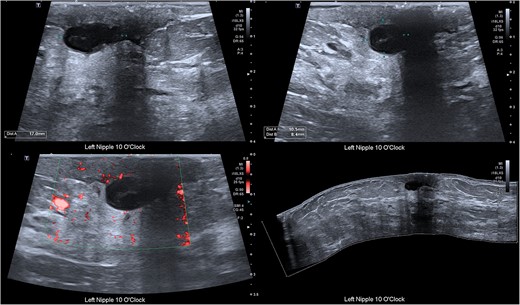

A 35-year-old non-lactating G1P1 woman was diagnosed with acute left breast pain on a background of a retroareolar lump. The patient experienced symptoms for less than 6 months. She had a past medical history of depression and anxiety, and was a current smoker. She was also allergic to penicillin. On examination there was left breast periareolar induration and erythema with an upper inner quadrant palpable solid, tender lesion adjacent to the nipple (Fig. 1). There was no right breast abnormality and no evidence of regional lymphadenopathy. An ultrasound suggested an infected epidermoid cyst and aspiration revealed mixed anaerobic bacteria (Fig. 2). The patient was prescribed antibiotics (clindamycin), discharged with advice to cease smoking and outpatient follow-up was arranged. The patient had two further admissions to hospital each within days of discharge for persistent symptoms.

Ultrasound of the breast demonstrating a cystic structure adjacent to the nipple measuring approximately 17 mm × 11 mm × 8 mm with surrounding inflammatory changes and low-level internal echoes. No internal flow.